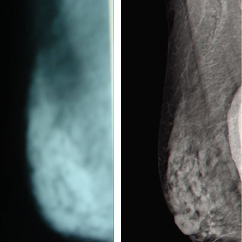

פאנל המומחים של 'אדם' - סרטן השד על שולחן הדיונים שלושה מהמובילים בתחום הטיפול בסרטן השד בקריה הרפוא...